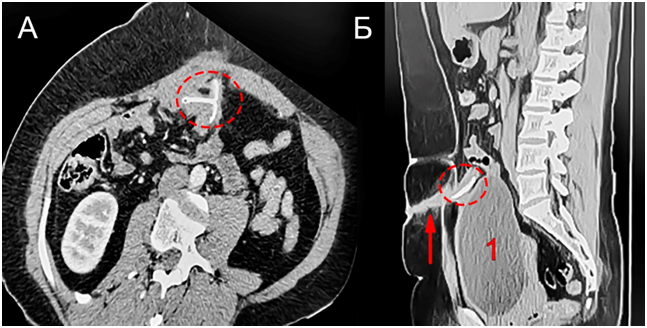

За 2,5 месяца до госпитализации в районной больнице по месту жительства проекционным доступом вскрыт абсцесс передней брюшной стенки. Эвакуировано 100 мл гноя (микрофлора неизвестна). Причина образования гнойника не выяснена. В послеоперационном периоде сформировался гнойный свищ. Для диагностики причины абсцедирования выполнена мультиспиральная компьютерная томография (МСКТ) брюшной полости, на которой в просвете тонкой кишки выявлено инородное металлическое тело размерами 25×25 мм Т-образной формы. Инородное тело по форме было похоже на внутриматочную спираль (рис. 2).

Рис. 2. МСКТ нижнего этажа брюшной полости. А – аксиальная плоскость, Б – сагиттальная плоскость Металлическое инородное тело (обозначено пунктиром) и свищевой ход (указан стрелкой). 1 – наполненный мочевой пузырь

Fig. 2. CT image of the lower abdomen demonstrating metallic foreign body (dashed line) and fistulous passage (arrow). 1 – full bladder. A – axial section, B – sagittal section